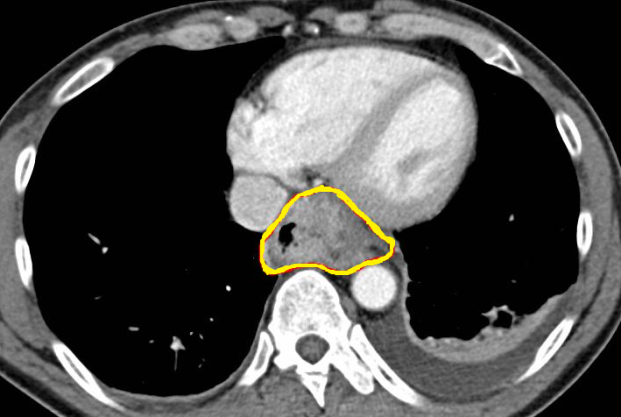

Παρουσία αέρα στο πυλαίο φλεβικό σύστημα, δευτεροπαθώς σε ισχαιμική κολίτιδα (Ευγενική παραχώρηση Dr. V. Penopoulos)